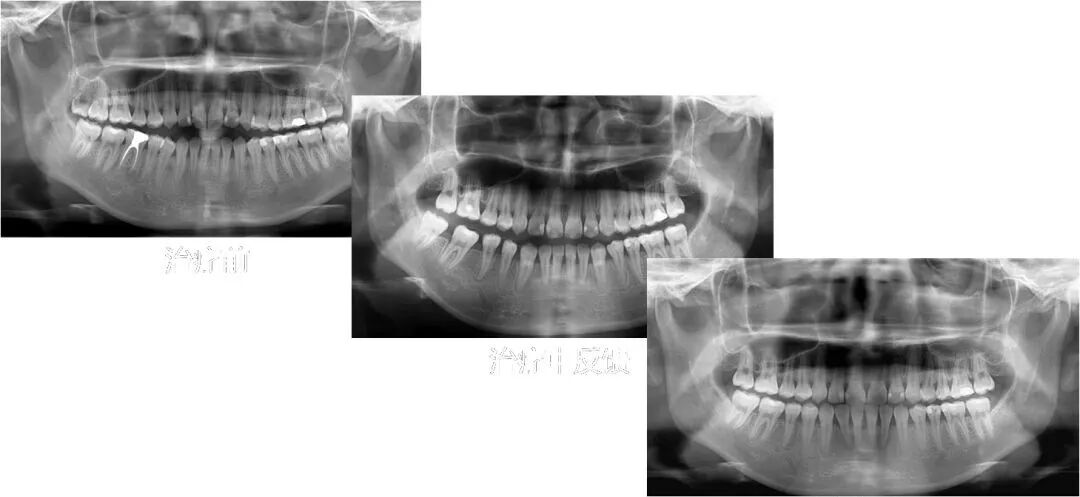

曲面体层片:

曲面体层片中,我们可以看到患者多个牙位存在高密度的充填影像。46牙可见根管充填影像,根充基本到位,近中根的根尖周存在局部低密度暗影,结合46牙的病史,这是一颗在外院行根管再治疗后观察了5年、影像学上并无好转的根尖周炎患牙,而且病人一直有咬合痛的症状,经我院牙体牙髓科会诊,治疗46牙需行根尖手术,并且认为预后比较差,而患者4个区的第三磨牙均存在,而且形态良好。

治疗后全景片显示牙根平行度尚可